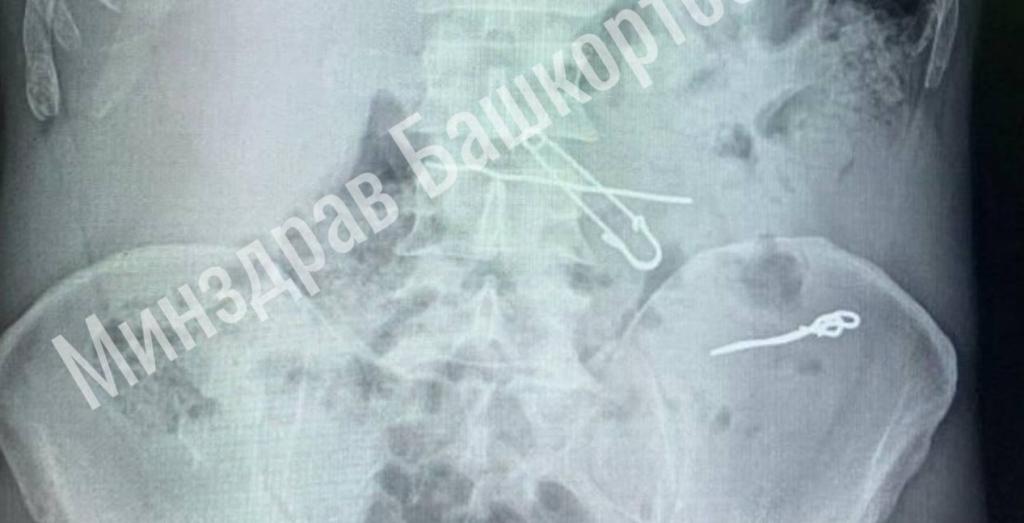

Мужчина обратился в больницу с жалобами на боли в животе. Обследование выявило в его толстой кишке несколько проволок и скрепок длиной от 47 до 90 мм, а в желудке — булавку и еще один кусок проволоки.

После госпитализации в отделение гнойной хирургии, команда хирургов провела операцию по удалению всех опасных предметов. В ходе операции была проведена контрольная рентгенография, чтобы убедиться в полном удалении инородных тел.